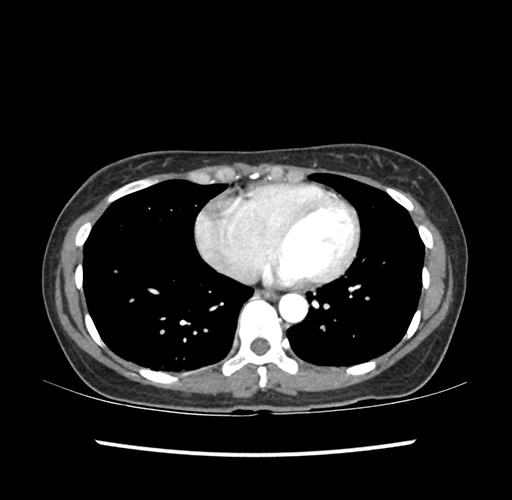

Imaging Analysis

Look through the patient's CT scan to identify any areas of concern for the necessary procedure.

Based on your CT findings, which issue(s) would give reason for "planned slowing down moment(s)" in this case?